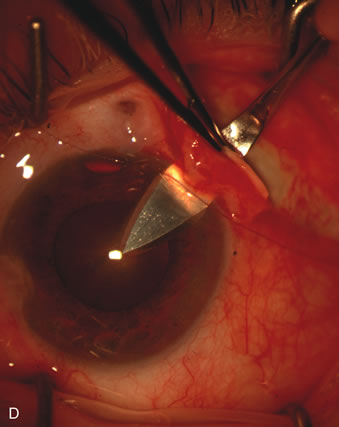

Fig. 4. Viscocanalostomy with deep sclerectomy and phacoemulsification. Nonpenetrating filtration procedures (NPFS) may be combined with phacoemulsification. Patients with mild disc damage and a history of limited topical drug therapy are the best candidates. Patients who require an IOP in the low teens are not good candidates for NPFS. By definition, NPFS is designed to lower IOP without penetrating into the anterior chamber, thereby avoiding the complications associated with trabeculectomy. Viscocanalostomy is intended to allow aqueous to percolate through a trabeculodescemetic membrane into a subscleral cavern created by the deep sclerectomy. The aqueous diffuses from the cavern into the dilated ostia of Schlemm's canal and into the episcleral venous plexus. A. Fashion a uniform 300-micron superficial scleral flap 1 mm into clear cornea. B. Construct a second 600-micron deep flap that facilitates the unroofing of Schlemm's canal, seen as the darker area. C. Use viscoelastic to dilate the ostia of Schlemm's canal. The major problem with viscocanalostomy is the eventual closure of the ostium decreasing flow to the episcleral plexus. D. Dissect the deep flap anteriorly into clear cornea creating the trabeculodescemetic membrane. This membrane is clearly seen between the scleral spur and the bend of the deep flap. The integrity of this membrane ensures the nonpenetrating portion of the surgery. Another problem with NPFS is the eventual fibrosis of this initially transparent membrane requiring goniopuncture. E. Deep sclerectomy gets its name from removal of the deep flap. Removal of this flap creates the potential subscleral space for accumulation of aqueous before it enters Schlemm's canal and exits the episcleral venous plexus. After removal of the deep flap, the superficial flap is sutured into place and conjunctiva closed. Approximately half of these procedures develop a shallow bleb.